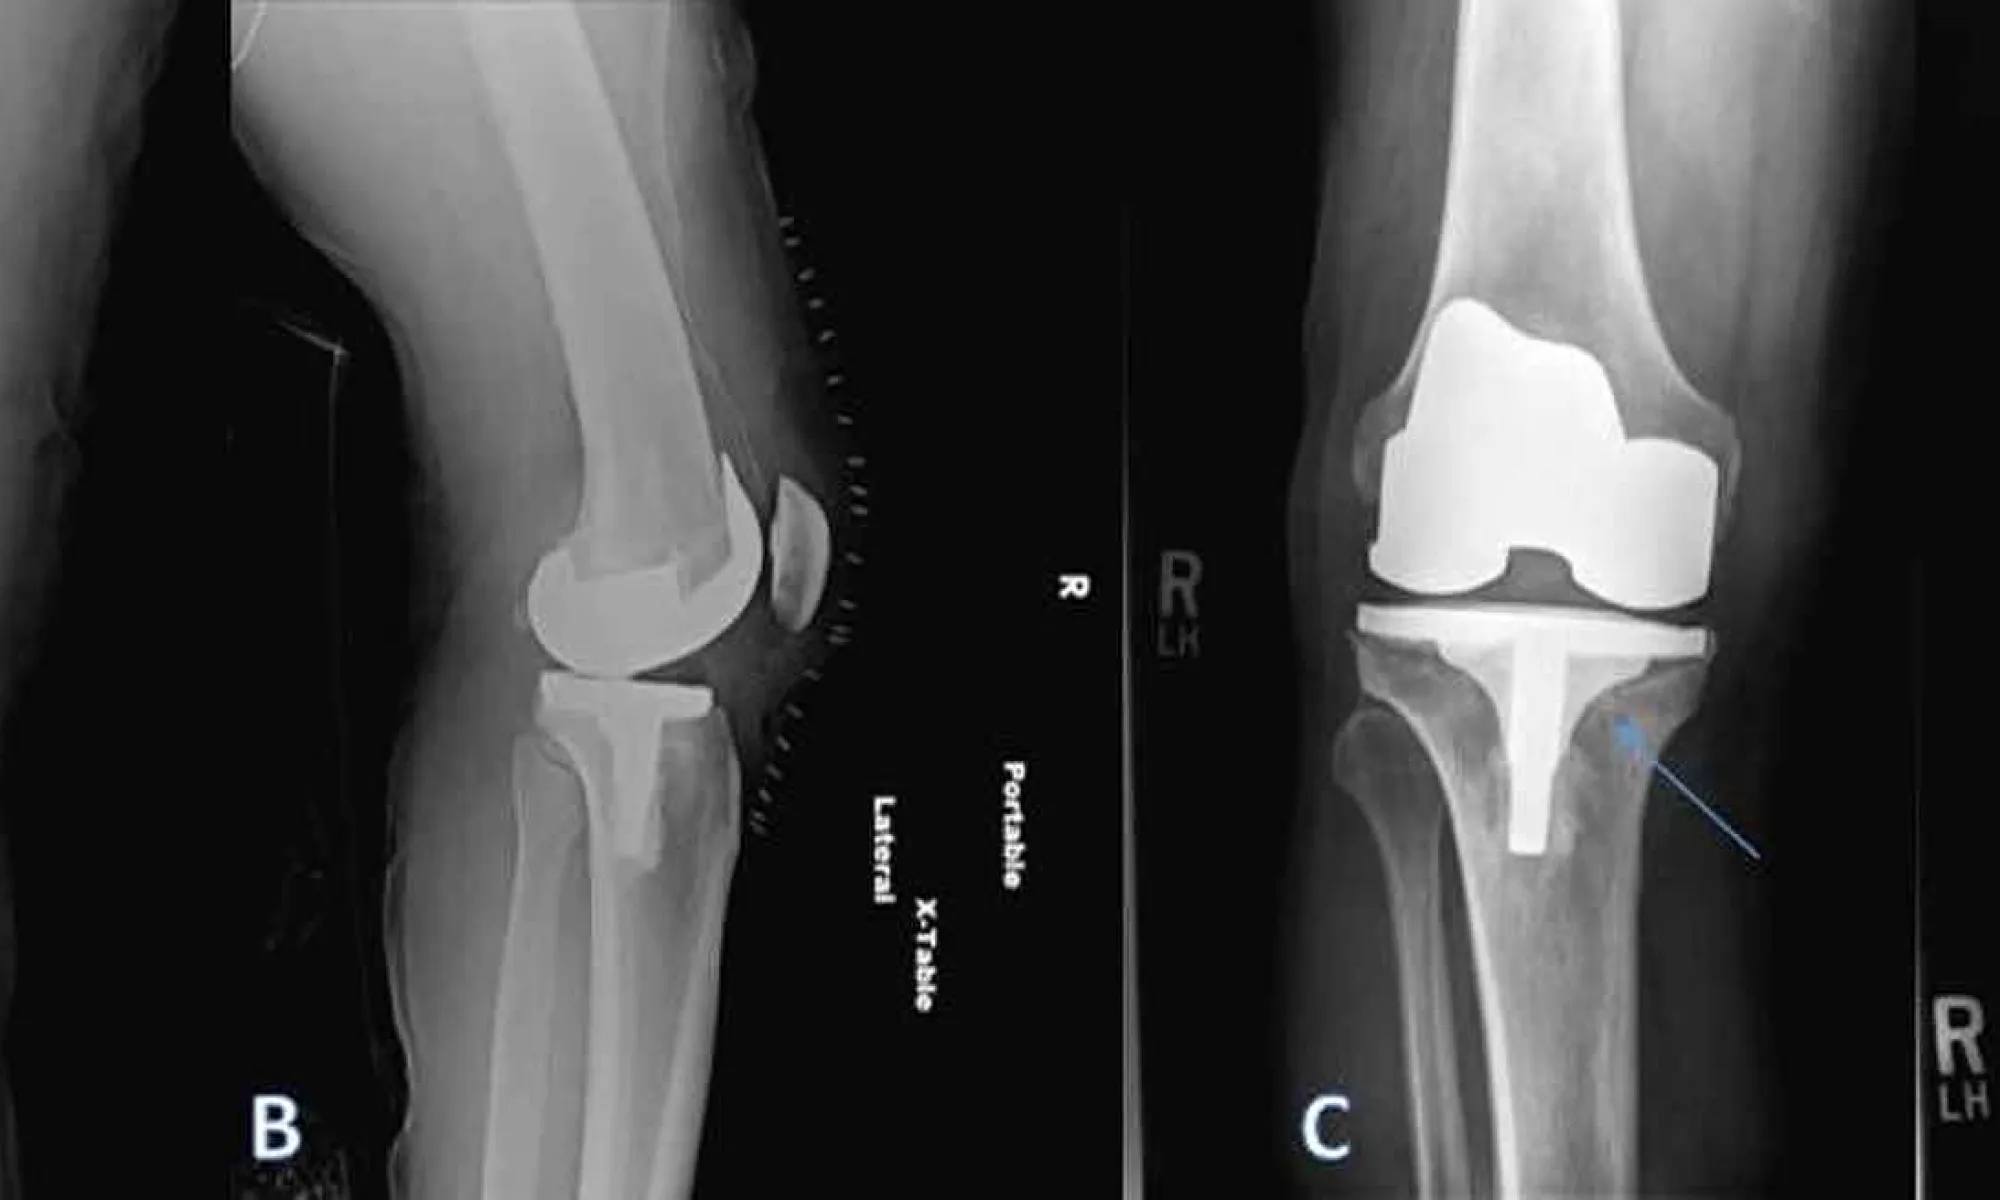

(A and B) A 69‐year‐old woman underwent bilateral robot‐assisted total Robot Assisted Tka total knee arthroplasty (tka) is a successful treatment for tricompartmental knee arthritis. in orthopedics, a robotic tkr is designed to decrease the mistakes associated with bone cuts and prosthesis. Robot Assisted Tka.